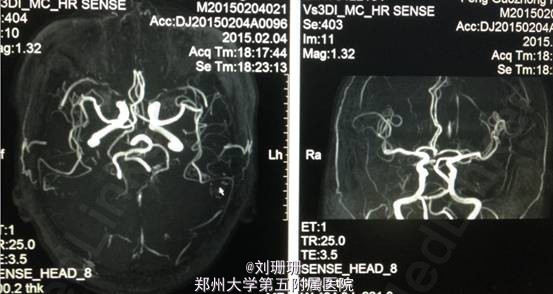

血压 120/80mmHg,神志清,精神一般,面部表情减少,构音清,言语顿挫欠流利,对答反应时间较长,查体欠合作。双侧额纹对称,双眼球各方向活动自如,无眼震,复视及视野缺损,双侧鼻唇沟对称,伸舌基本居中,咽反射灵敏。双上肢肌力Ⅴ级,双下肢肌力Ⅳ级,肌张力偏高无震颤,双侧腱反射对称,双侧巴氏征阴性。痛觉对称,共济运动因智能下降不能配合。双肺呼吸音粗,心率72次/分,律齐,双下肢无水肿。MMSE 18分。 头颅DWI提示双侧侧脑室旁对称性异常信号,结合病史符合一氧化碳中毒脑缺氧缺血所致的脑白质脱髓鞘。